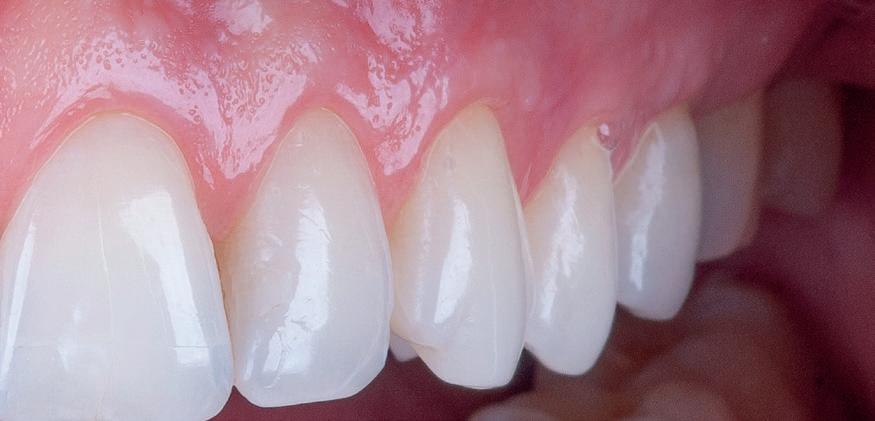

• Similar altor tehnici din stomatologie, procedurile utilizate pentru augmentarea țesuturilor moi ale rădăcinilor denudate au evoluat de-a lungul anilor. Accentul se pune astăzi pe cele minim invazive, parodontologii depunând eforturi pentru o predictibilitate mai mare, cu morbiditate locală scăzută. Regăsiți descrisă tehnica smile (labială sulculară internă modificată) cu tunelizare combinată cu xenogrefă și PRF, care necesită semnificativ mai puține instrumente decât alte proceduri comparabile.

Tehnica SMILE pentru augmentarea gingivală: etape, cazuri clinice

• Chirurgia implantară cu cea mai inteligentă planificare și mai precisă execuție va necesita în continuare un finisaj protetic care funcționează biomecanic și realizează o estetică naturală ideală individuală. Dacă există un aspect al tratamentului protetic cu provocări în era digitală, acesta ar consta în munca artistică minuțioasă a ceramistului, cu modelarea și pictarea dinților pentru a imita natura.